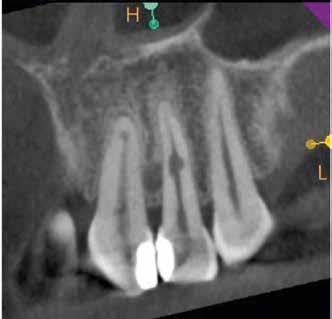

A 28 éves pácienst gyulladásos IRR kezelése céljából irányították a rendelőnkbe. A jobb felső nagymetszőfogáról készített periapikális röntgenen egyértelműen látható volt a lézió. A várható prognózis megállapítása, valamint kezeléstervezés céljából az érintett területről CBCT-felvétel készült (8. a–e ábra). A háromdimenziós képen látható volt a gyökér labiális falán lévő perforációs nyílás, valamint az ezt körülvevő bukkális kortikális destrukciója. A terület sebészi feltárását a bal felső nagymetszőfogtól a jobb felső szemfogig intrasulcularisan vezetett metszésből végeztük el. A lebeny elemelését követően egy exkavátor segítségével eltávolítottuk a reszorbciós üreget kitöltő granulációs szövetet (9–11. ábra), majd hagyományos

8. a–e ábra: A kiindulási röntgen (a) és a kiindulási állapotról készített CBCT-felvétel (b–e). A felvételen jól látható a csatornafal és a bukkális kortikális perforációja.

MTA-val (Mineral Trioxide Aggregate; Harvard Dental) töltöttük fel. A léziótól koronális irányban elhelyezkedő gyökércsatorna-szakaszt meleg guttaperchával zártuk, majd az MTA-val kitöltött üregre egy kis darab kollagénszivacsot helyeztünk és a lebenyt varratok segítségével eredeti pozíciójában rögzítettük (12. a–b; 13. a–b. ábra). A fog koronai részét Gradia kompozit tömőanyaggal állítottuk helyre (GC; 14. a–b; 15. ábra). Kontrollvizsgálatra két (16. a–b ábra) és négy évvel (17. a–b ábra) később került sor. A kontrollfelvételeken a bukkális kortikális jelenléte volt észlelhető. A fog körüli parodoncium egészséges volt, valamint a páciens sem számolt be tünetekről.

16. a–b ábrák: A két évvel később készített kontroll CBCT-felvétel. – 17. a–b ábrák: A négy évvel később készített kontroll CBCT-felvétel.